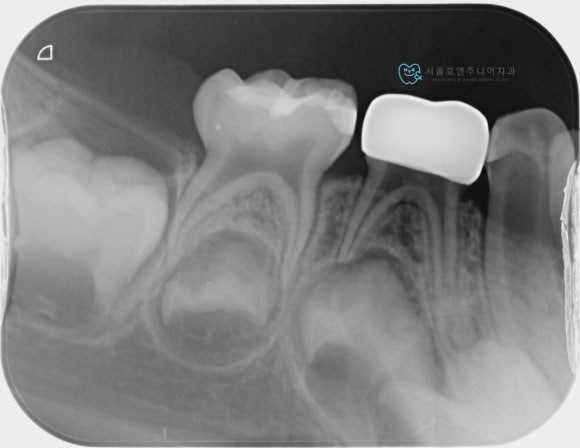

엑스레이에서 확인해보면 가운데 치아는 신경치료하지 않은 치아임을 알 수 있고, 크라운이 뜨거나 하지 않고 정확히 잘 들어갔음을 알수 있습니다. 크라운의 양쪽 치아도 눈으로봐서는 치료한 치아인지 알 수 없을 정도로 깔끔하게 레진으로 잘 치료되었습니다.

맞는 사이즈의 크라운 접착 후 모습입니다. 역시 유치 지르코니아크라운은 예뻐요^^엑스레이에서 확인해보면 가운데 치아는 신경치료하지 않은 치아임을 알 수 있고, 크라운이 뜨거나 하지 않고 정확히 잘 들어갔음을 알수 있습니다. 크라운의 양쪽 치아도 눈으로봐서는 치료한 치아인지 알 수 없을 정도로 깔끔하게 레진으로 잘 치료되었습니다.